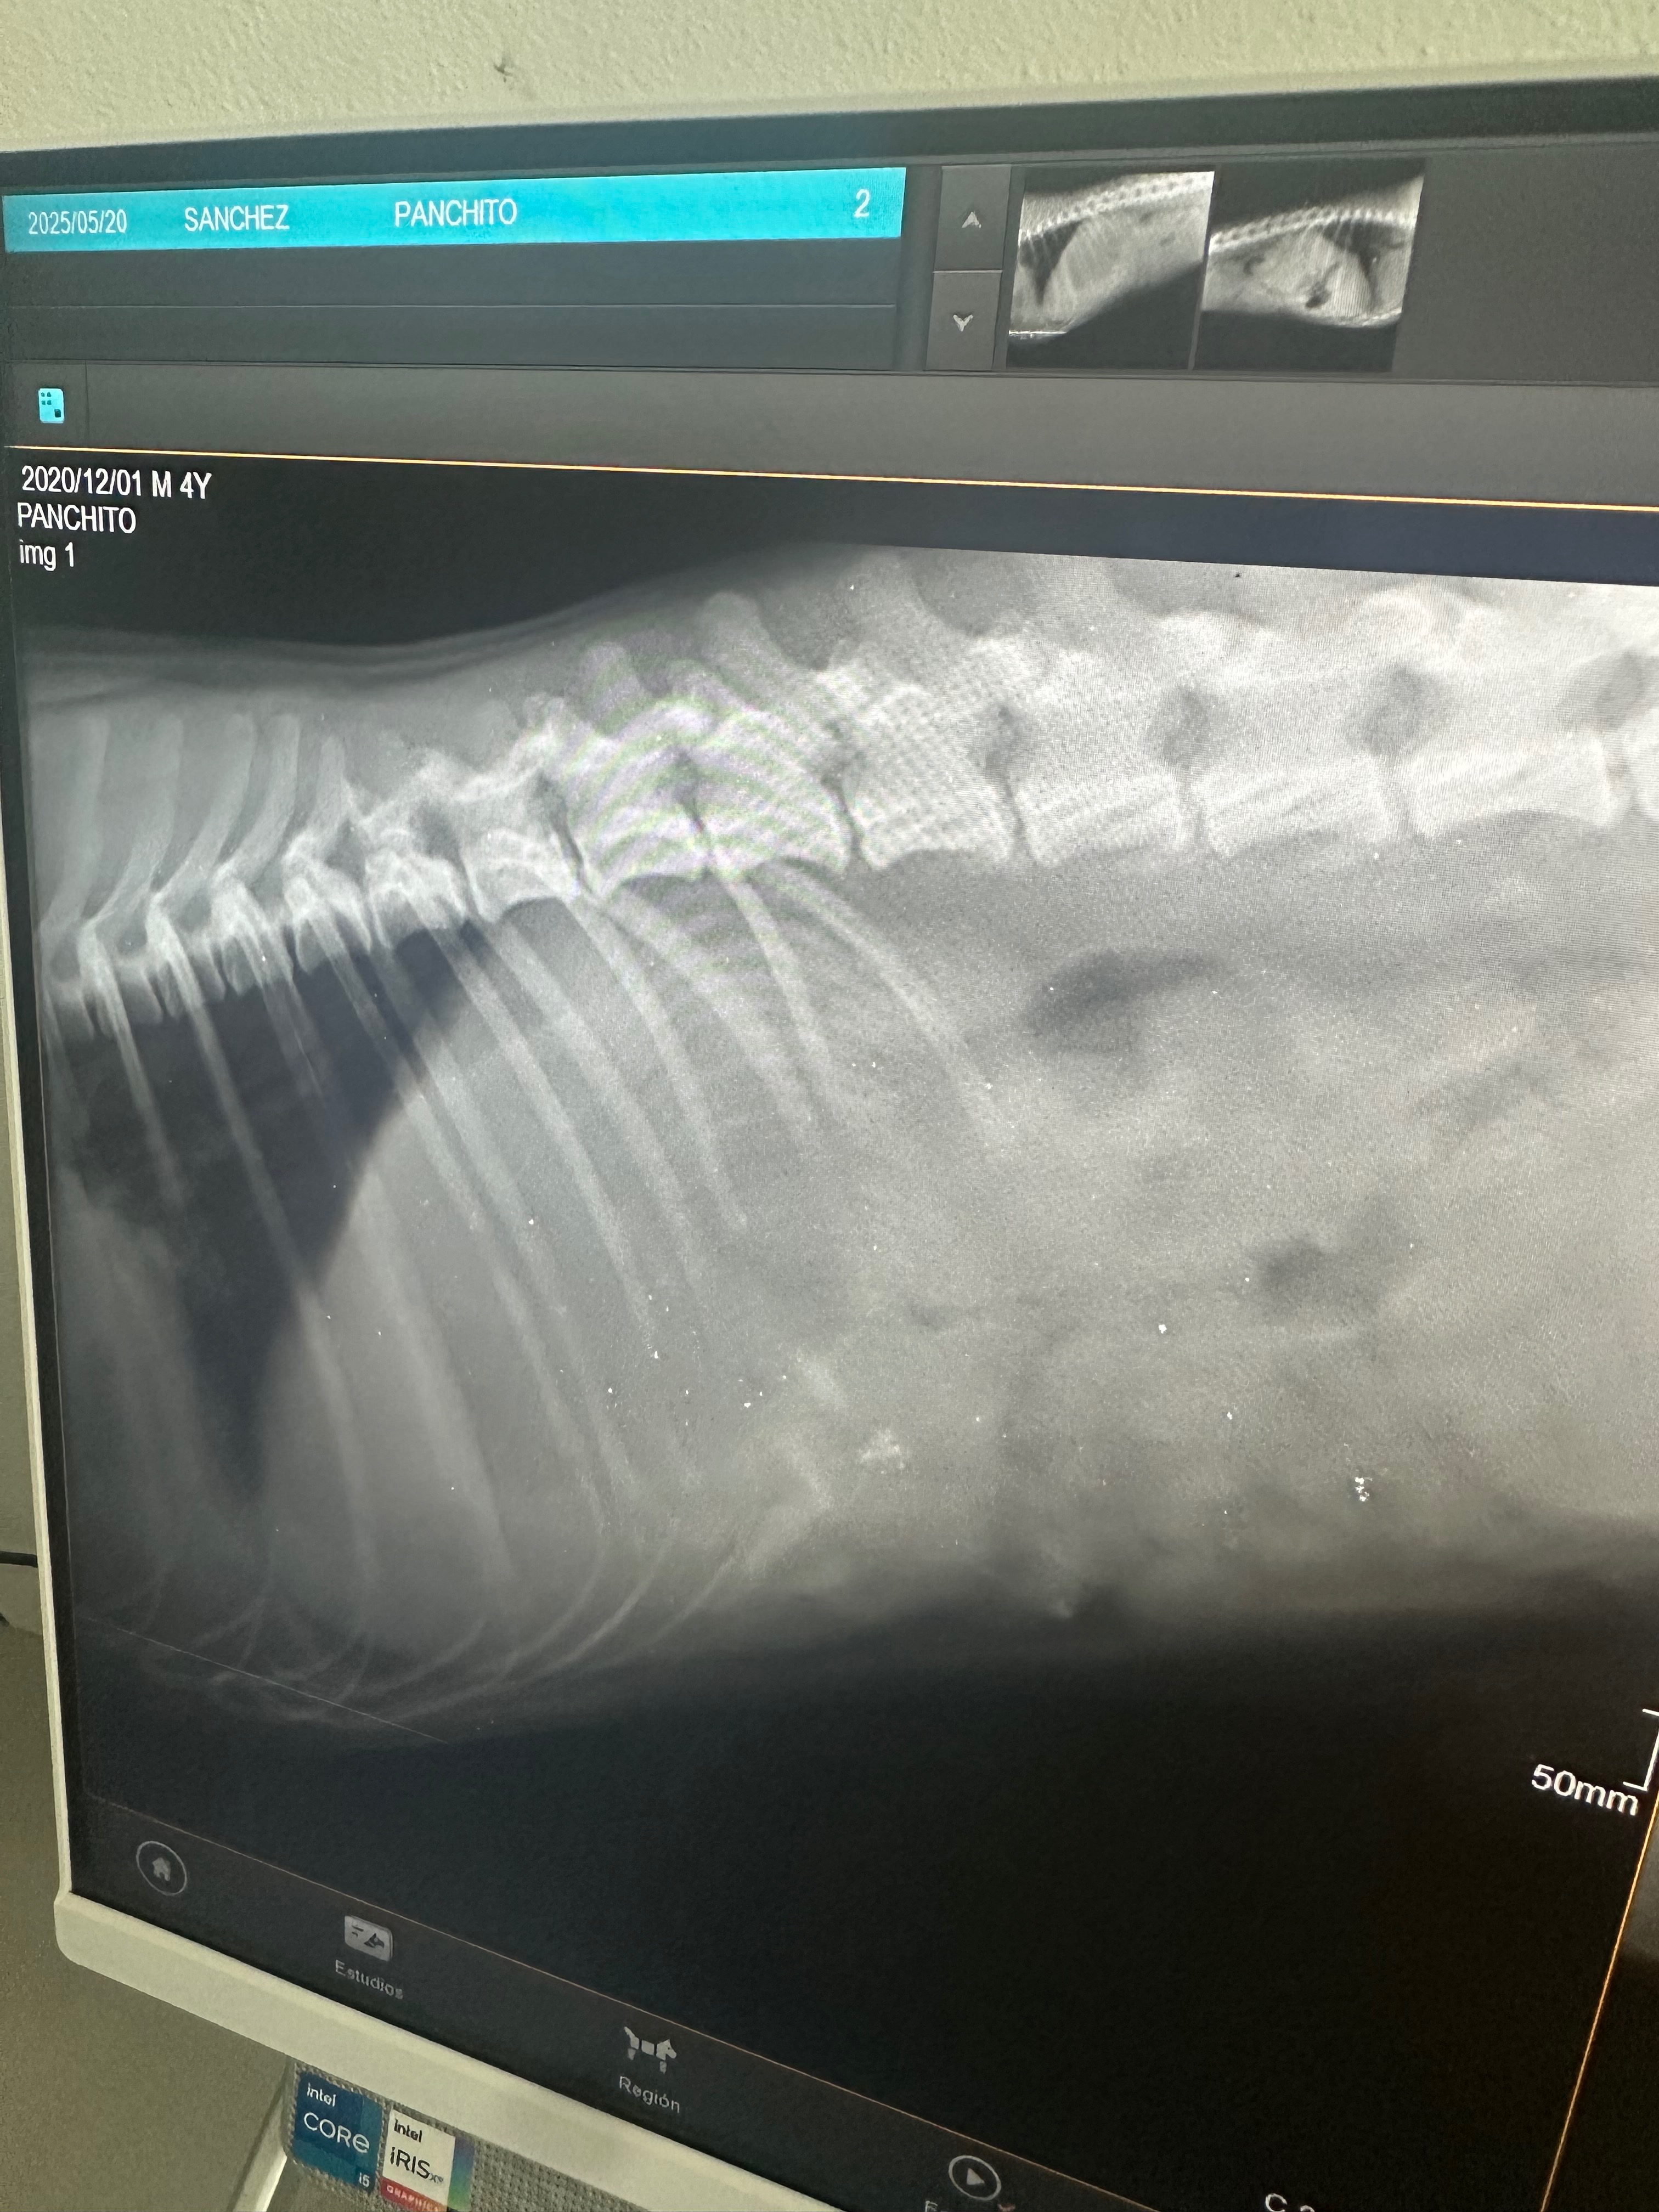

Hola me llamo panchito por andar de cómelon me comí un hueso de pollo gigante y se me atoró en mi estómago